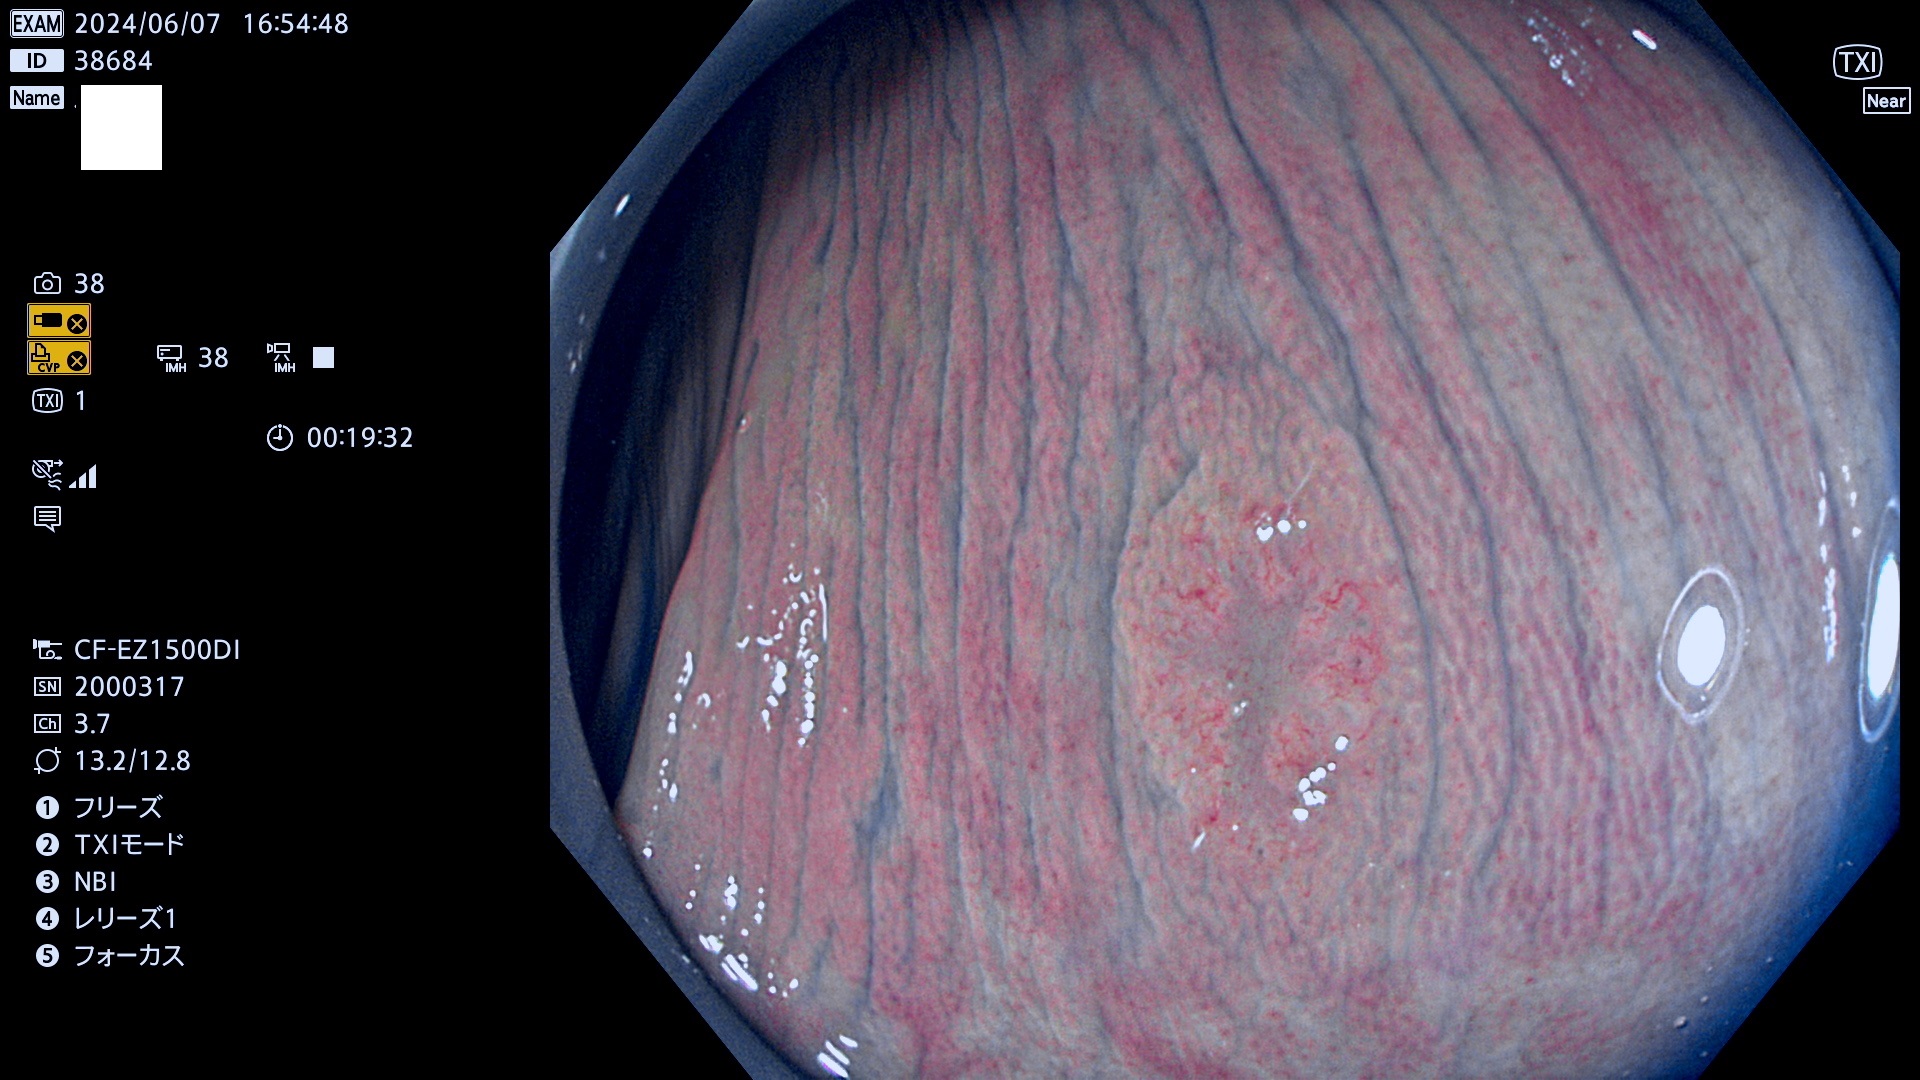

今週のUb、Uc型腺腫

表面型腺腫(Flat Adenoma)の中で、完全に平坦な物をUb、陥凹している物をUcと呼びます。平坦隆起型(Ua)よりも、発見が難しく危険な病変です。

毎週の検査(木・金・土・日)に発見されたUb、Uc型・腺腫を、その週の日曜の夜にUPし1週間、提示します。

抽出の対象期間 2024年6月6日〜6月10の5日間(50件の検査)7件 (7/50=14%)